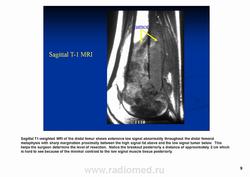

Остеосаркома